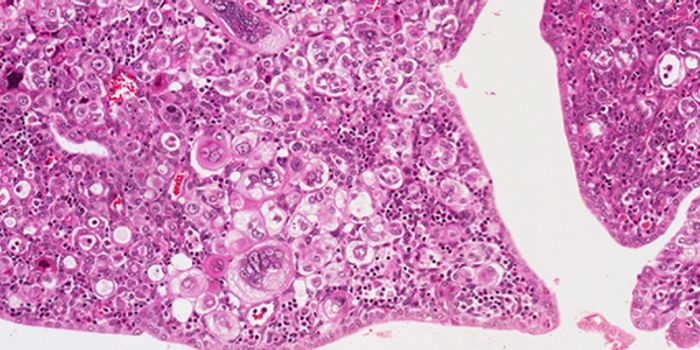

MAR 20, 2014CancerAccording to the American Cancer Society, cancer will occur in more than 1.6 million individuals this year in the United ...

MAR 19, 2015CancerResearchers at the Stanford University School of Medicine have discovered that when a certain aggressive leukemia is cau ...